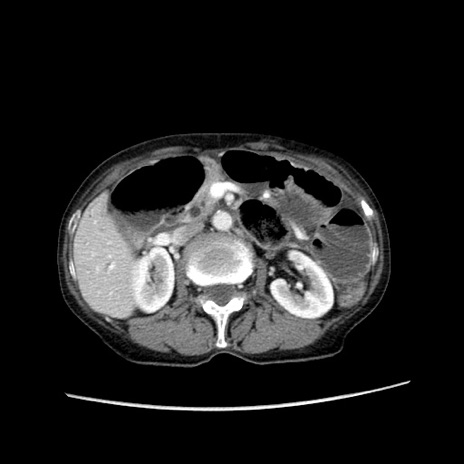

冠状断像

【症例】80歳代女性

【主訴】胸のつかえ感

【現病歴】約9時間前に食後から胸のつかえた感じあり、嘔吐あり、来院。

【既往歴】胃癌(全摘)、胆摘、虫垂炎

【身体所見】心窩部に圧痛あり、反跳痛なし。

【データ】WBC 5700、CRP 0.05